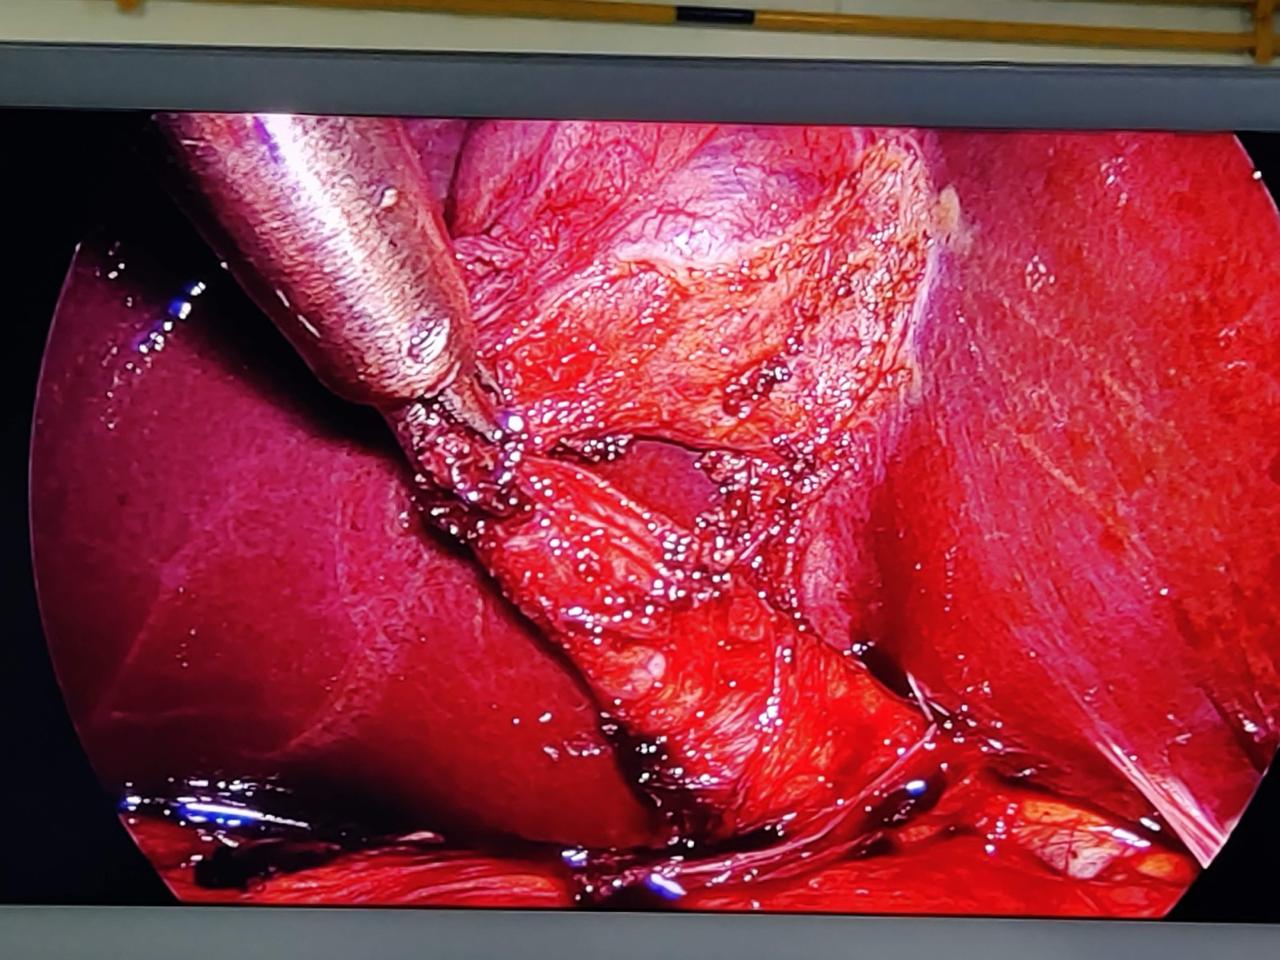

Welcome to our gallery, where you can explore a visual journey of our state-of-the-art surgical facilities, advanced medical equipment, and the exceptional care provided by our dedicated team. Here, you’ll find images showcasing our modern operating rooms, comfortable recovery areas, and the skilled professionals who ensure the highest standards of patient care.

Our gallery also features before-and-after photos of successful procedures, highlighting our commitment to transformative, evidence-based surgical practices. We invite you to browse through and witness the excellence and compassion that define our surgical practice.